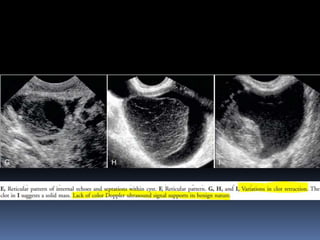

This document contains an image gallery from Dr. Mohit Goel showing various uterine anomalies and ovarian cysts. It includes images of an arcuate and unicornuate uterus, endometritis, a twisted ovarian pedicle, dermoid cysts of varying sizes and echogenicity containing hair, fat, and calcifications, and a combination dermoid cyst showing both mesh and plug structures. The gallery provides ultrasound images of different gynecological conditions for medical education and reference.